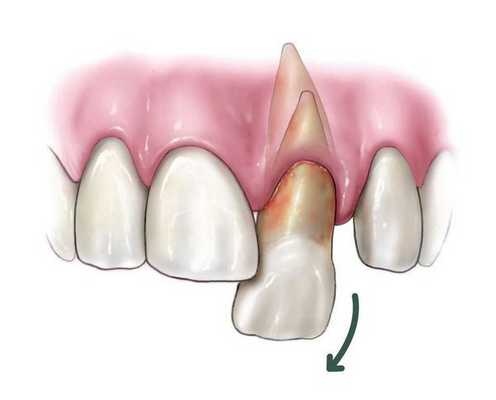

Неполный вывих характеризуется сохранением зуба в его лунке и сопровождается разрывом части волокнистых структур, окружающих и удерживающих зуб, либо растяжением волокон в той или иной степени. Для данной патологии характерно изменение положения коронки зуба и корня в зубном ряду по отношению к стенкам альвеолы. Зуб имеет неправильное положение вследствие смещения в вестибулярную ( в сторону губы) или оральную сторону, в сторону соседнего зуба или поворота вокруг оси. Это приводит к нарушению формы зубного ряда. Неполный вывих может сочетаться с переломом коронки, корня зуба или альвеолярного отростка.

Согласно Международной классификации болезней 10 пересмотра (МКБ-10) код вывиха зуба — S03.2. Различают три вида [1] [3] :

- неполный вывих (при этом зуб частично остается в костной лунке);